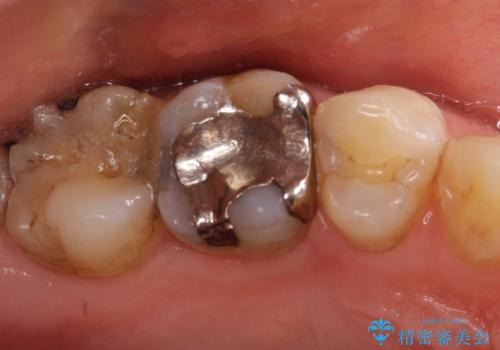

- 奥歯がかけたことを主訴に来院されました。

オールセラミッククラウンにて修復治療を行っております。

歯の破折強度を高めるためにクラウンによる修復を希望され、治療を行っております。